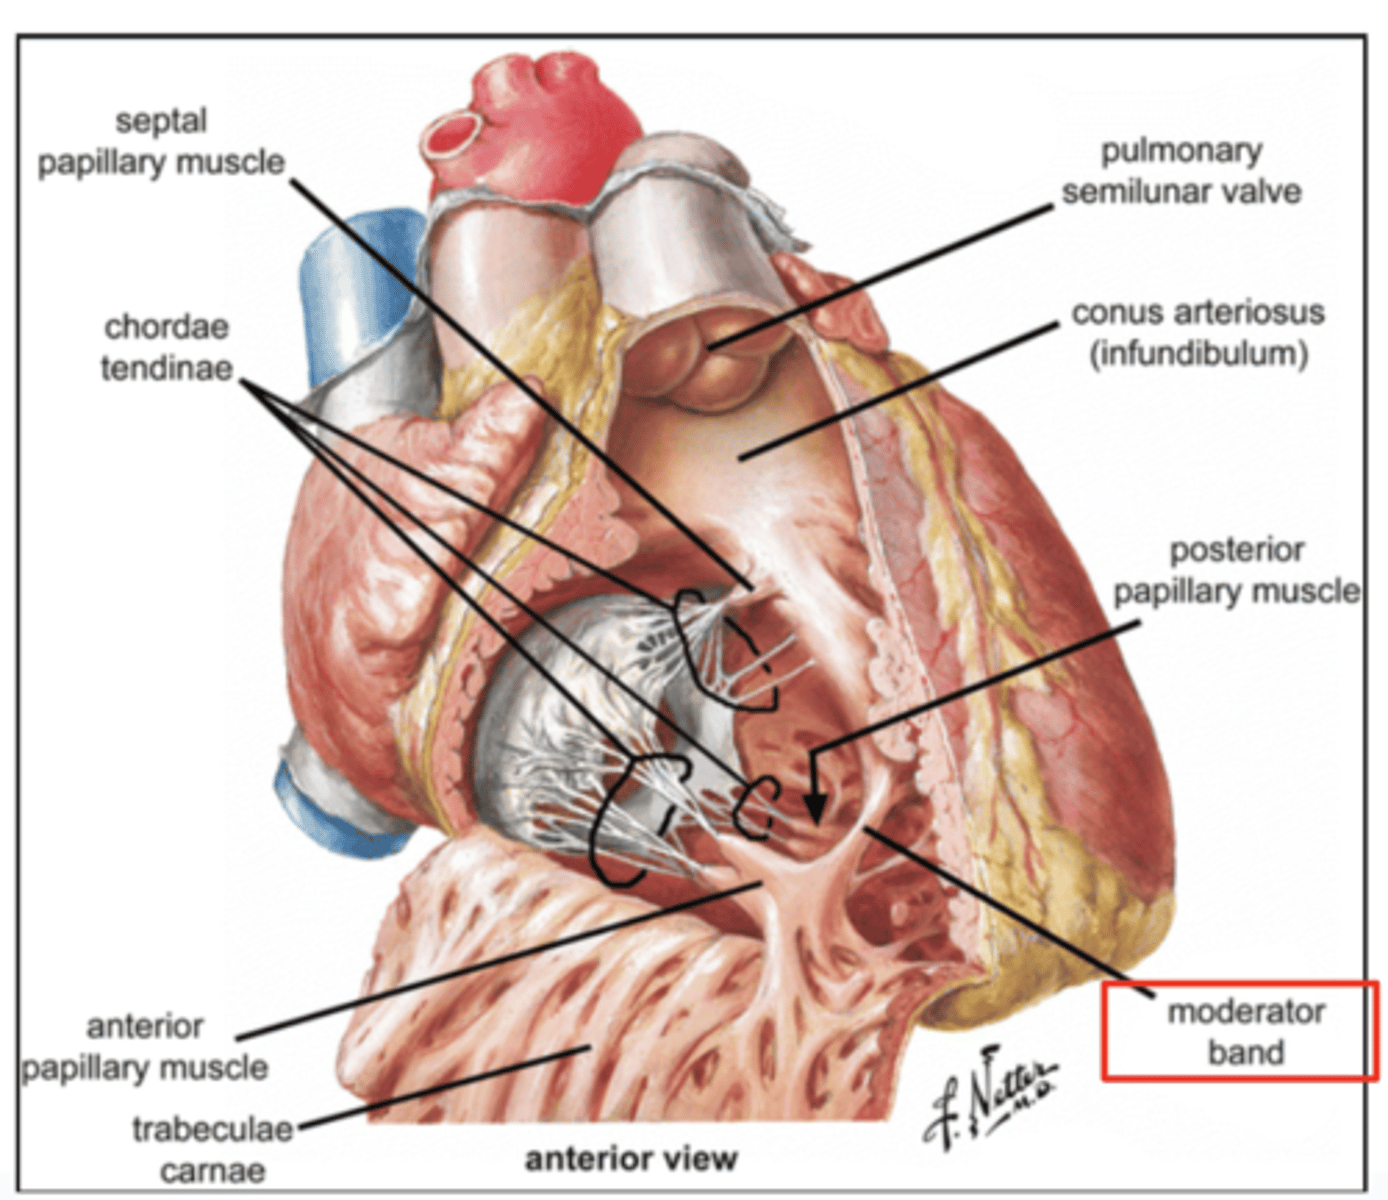

Describe the two portions of the medial/septal face/wall of the right ventricle.

infundibulum or outflow region or conus arteriosus (smooth and membranous)

trabeculae carnae (muscular and irregular)

What is the septomarginal trabeculae (or moderator band)?

Part of the conduction system of the heart.

electrical waves pass through this band to reach the papillary muscles.

What role does the moderator band play in the conduction system?

Allows the wave to reach the papillary muscles, inducing their contraction simultaneously with that of the ventricles.

REMEMBER: PAPILLARY MUSCLES ACT THROUGH THE CHORDAE TENDINAE TO CONTROL THE TRICUSPID AND MITRAL VALVES.